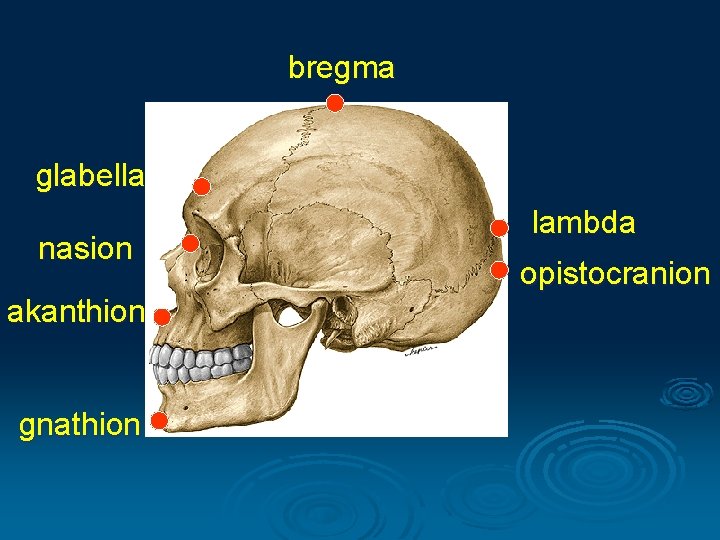

I. Cranimetry Points § Unpaired: nasion, glabella, bregma, akanthion, lambda, orale, opisthocranion, basion, staphylion § Binate: pteryon, porion, euryon, zygion, gonion, endomolare

bregma glabella nasion akanthion gnathion lambda opistocranion

Size of the skull Length: glabella - opisthocranion Width: euryon - euryon High: bregma - basion

Size of the face Length: nasion - gnathion Width: zygion - zygion